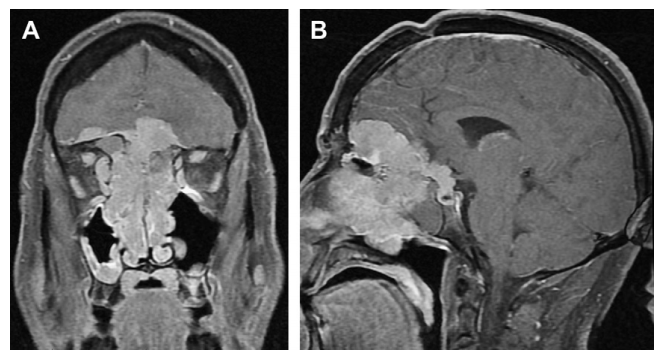

(A)冠状位t1加权增强磁共振成像(MRI)。该患者之前做过外皮瘤切除术。患者无病超过5年,但在6个月的时间里,迅速发展为恶性脑膜瘤,较终死亡,没有额外的治疗。(B)矢状位t1加权增强MRI恶性脑膜瘤来自(A)。